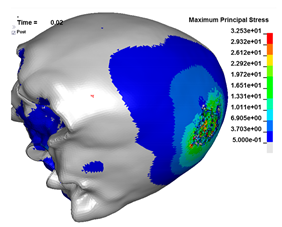

| Cyclist accident—SUV impacts at 40 km/h. Skull fractures can be clearly validated during autopsy or CT medical examination. Research important for cyclist’s helmet optimization and forensic science. |  50th-percentile male on a MB bicycle model, coupled with a FE SUV. |  Cyclist’s skull—max principal stress and fracture pattern on periosteum and endosteum [MPa]. |

- Acceleration, intracranial pressure, stress and strain, which have been postulated as head injury mechanisms and thereby may be used as predictions of various head injuries.

| Head Injury | Criteria | Threshold |

| Bone (skull) fracture | Maximum principal stress (diploe layer) | 20 MPa |

| Maximum principal strain (cortical layer) | 0.42% | |